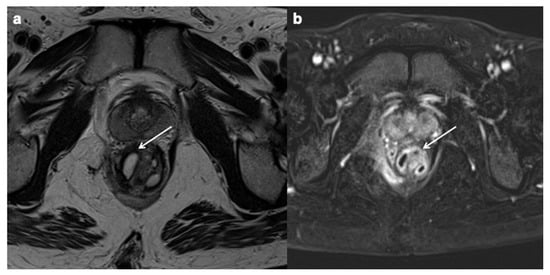

- Criado, J.D.M.; Del Salto, L.G.; Rivas, P.F.; Del Hoyo, L.F.A.; Velasco, L.G.; Vacas, M.I.D.P.D.L.; Sanz, A.G.M.; Paradela, M.M.; Moreno, E.F. MR Imaging Evaluation of Perianal Fistulas: Spectrum of Imaging Features. RadioGraphics 2012, 32, 175–194. [Google Scholar] [CrossRef]

- Gecse, K.B.; Bemelman, W.; Kamm, M.A. A global consensus on the classification, diagnosis and multidisciplinary treatment of perianal fistulising Crohn’s disease. Gut 2014, 63, 1381–1392. [Google Scholar] [CrossRef] [Green Version]

- Parks, A.G.; Gordon, P.H.; Hardcastle, J.D. A classification of fistula-in-ano. Br. J. Surg. 1976, 63, 1–12. [Google Scholar] [CrossRef] [PubMed]